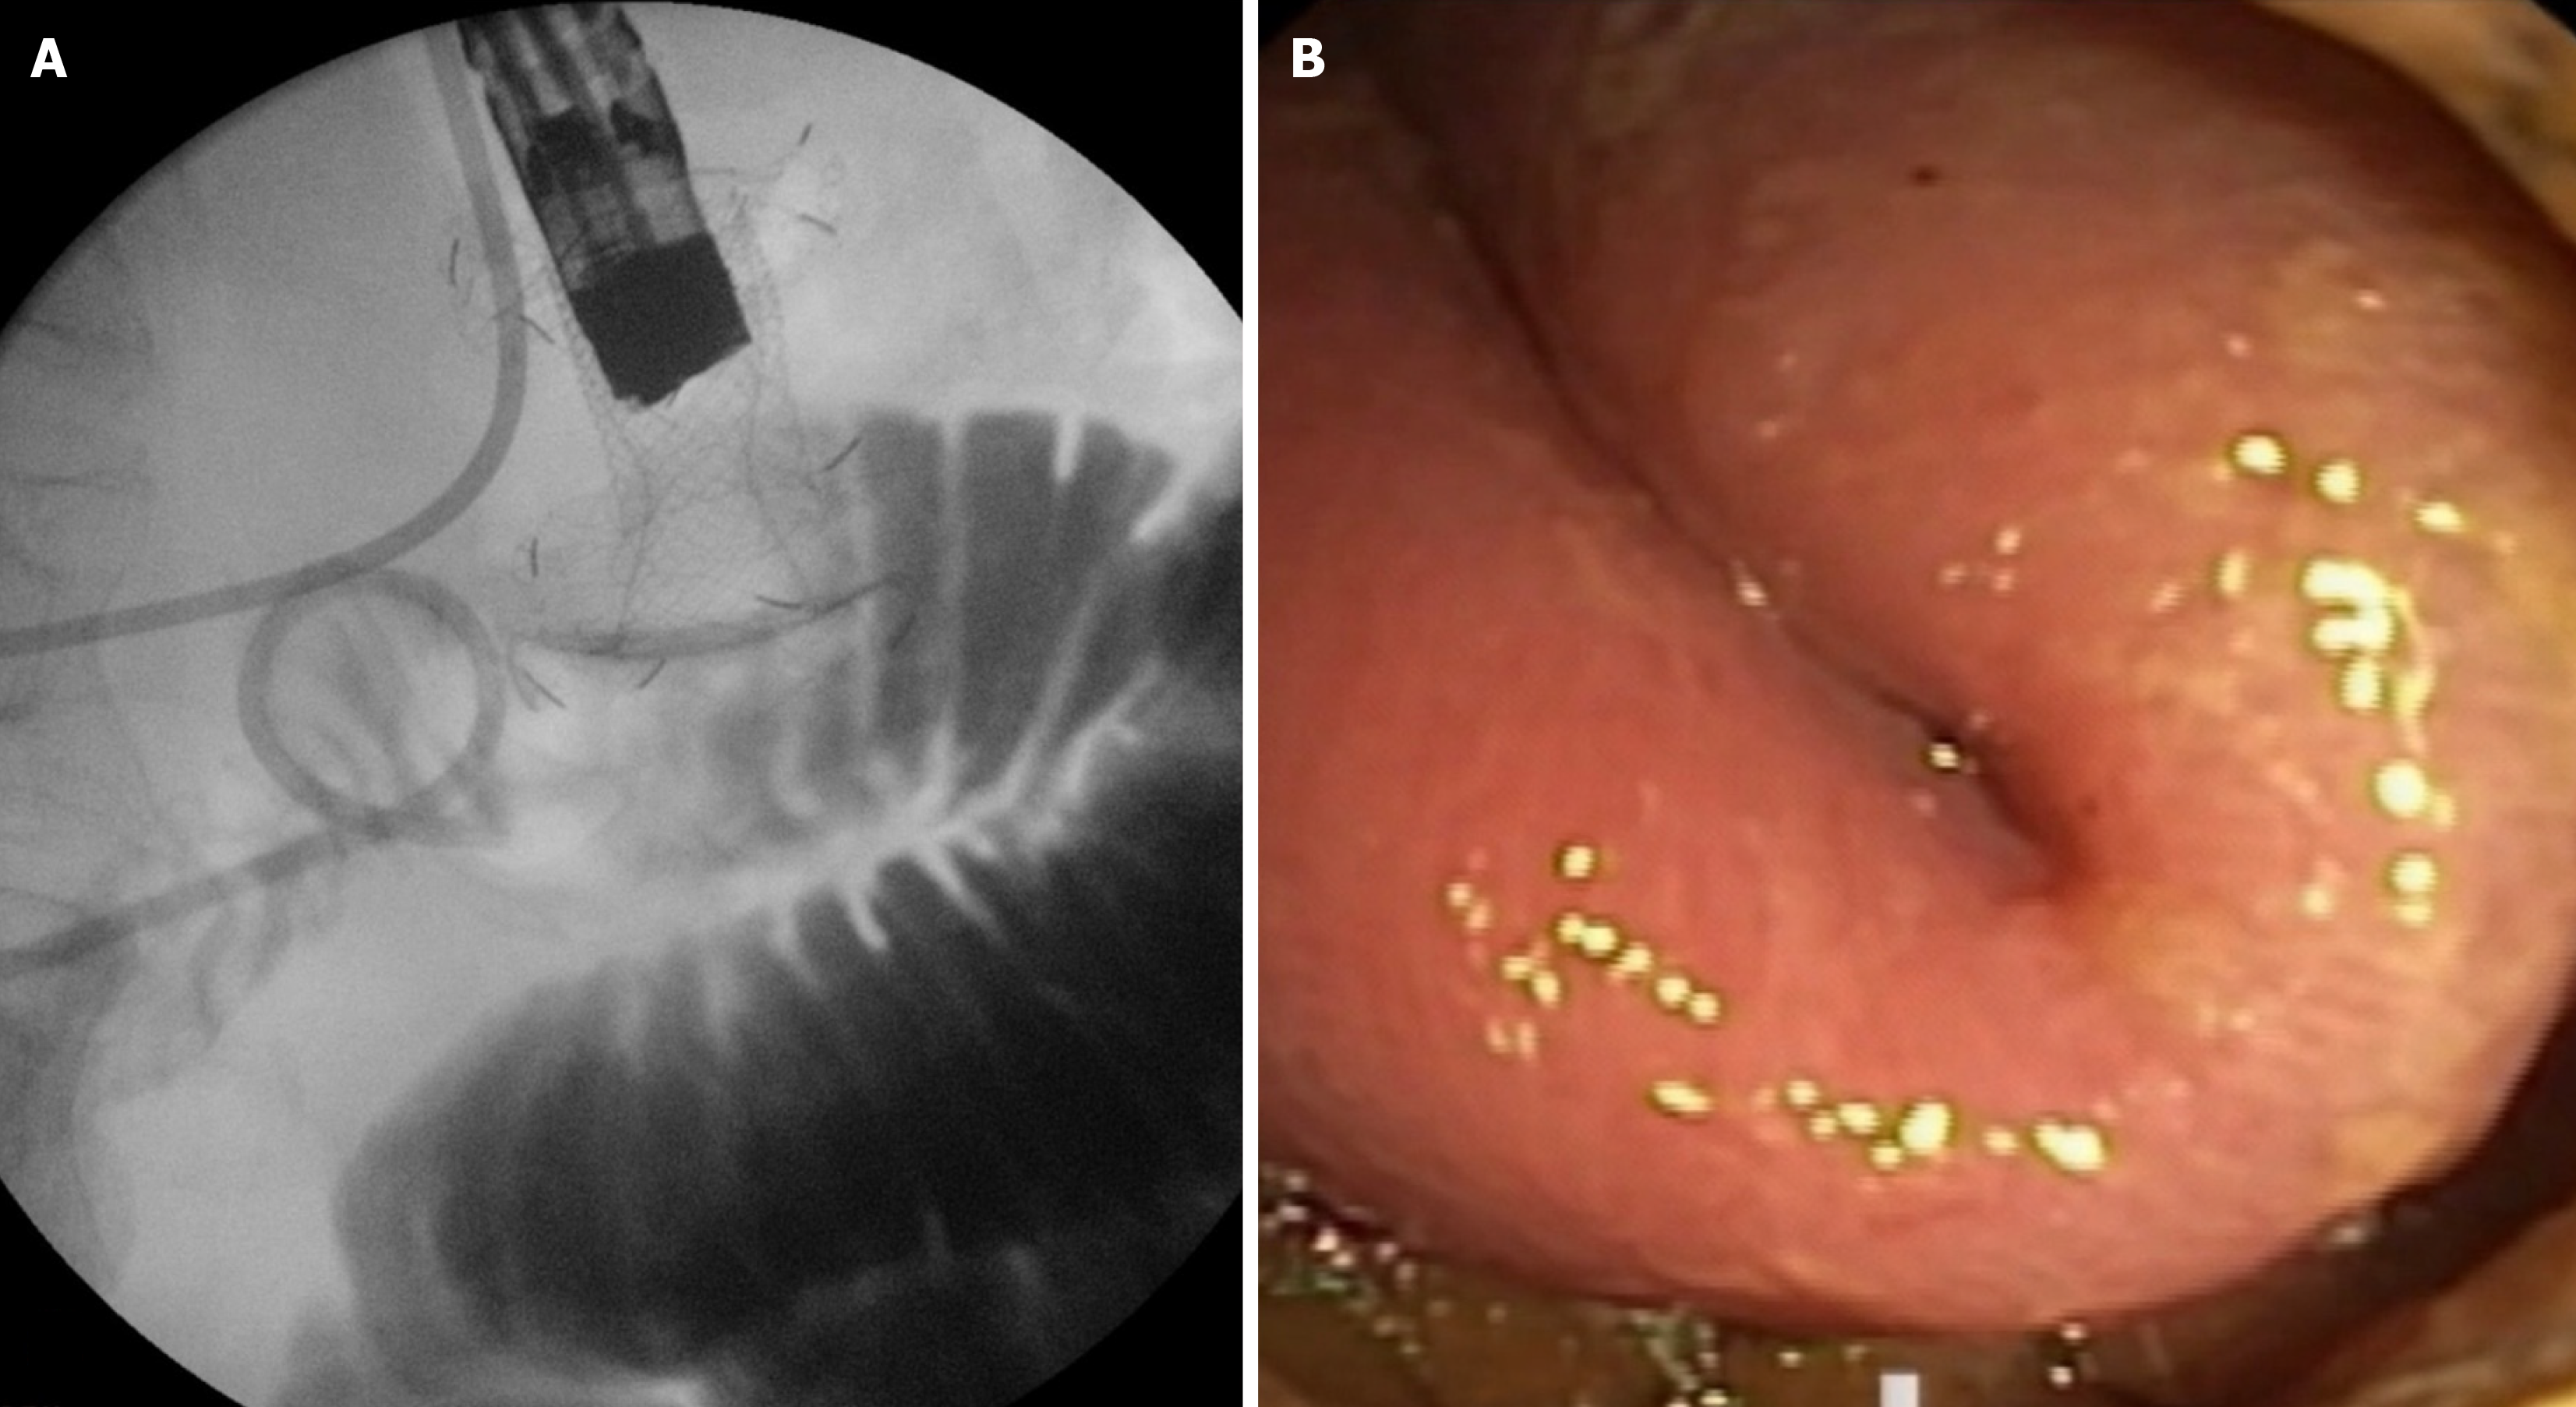

Figure 3 Type I stent misdeployment.

A: Fluoroscopic view showing the distal flange of the lumen-apposing metal stent deployed in the peritoneal cavity while the proximal flange remains in the stomach; B: Endoscopic view confirming the incomplete anastomosis with the small bowel intact.